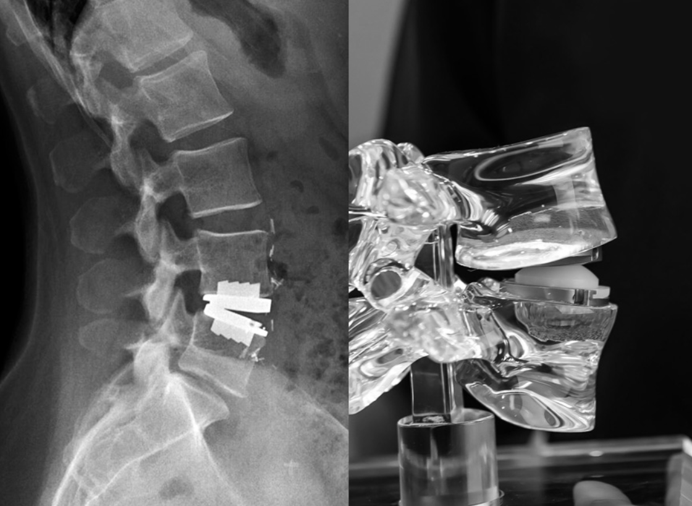

What is Artificial Disc Replacement?

A surgery where a damaged spinal disc is removed and replaced with an artificial one that allows normal spine movement.

Artificial Disc Placement

The damaged disc is replaced with an artificial disc to maintain spine movement.

- Maintains flexibility of the spine